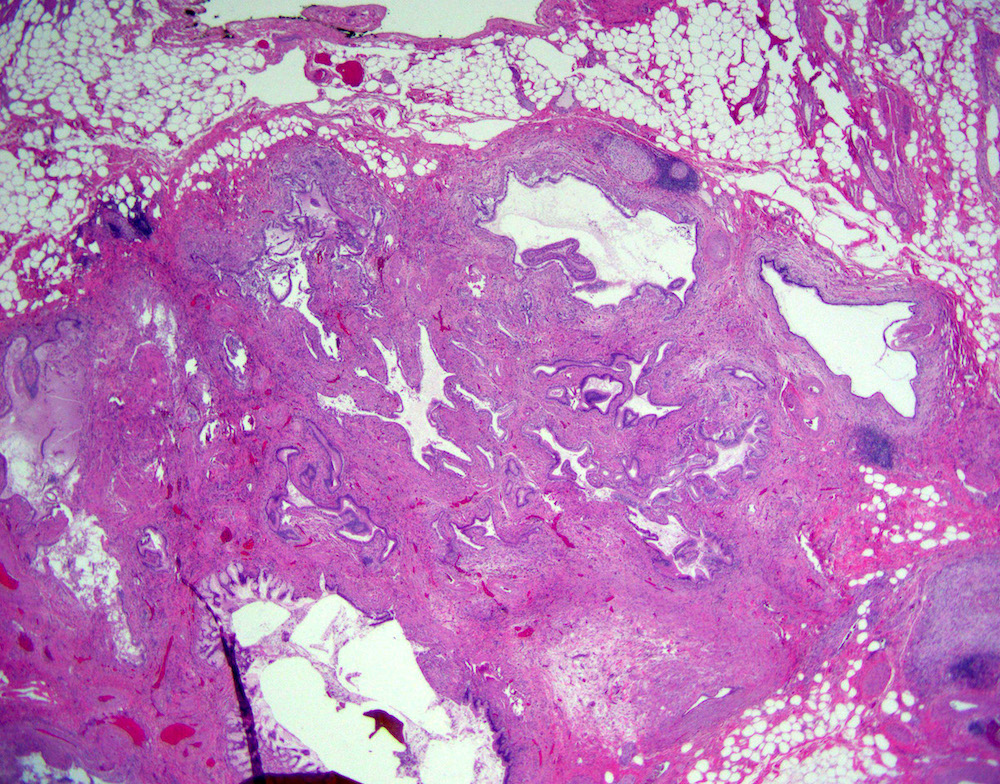

Microscopic (histologic) description

- Cystically dilated benign biliary glands accompanied by smooth muscle hypertrophy of gallbladder wall, thickened / fibrotic subserosa (StatPearls: Adenomyomatosis [Accessed 26 January 2021])

- Glands are distinct from the Rokitansky-Aschoff sinuses, which are epithelial diverticula, usually multifocal and occur throughout gallbladder secondary to injury, versus adenomyomatous nodule (distinct localized lesion of the gallbladder wall, 1 - 1.5 cm mural nodule in the fundus) (Am J Surg Pathol 2020;44:1649)

- May have reactive epithelial changes, papillary change and intestinal metaplasia (StatPearls: Adenomyomatosis [Accessed 26 January 2021])

- Rarely, benign glands are seen in proximity to nerves, appearing as perineural and intraneural invasion only in the subserosal layer (benign gland-like structures may migrate into nerves due to chemotactic factors or signaling substances with activation of cell receptors) (Am J Surg Pathol 2007;31:1598)

- Adenomyomatous nodules may rarely show dysplastic / carcinomatous transformation, whereas dysplasia in Rokitansky-Aschoff sinuses appears to be more common; however, the true association between adenomyomatous nodules and neoplasia has not yet been determined (Am J Surg Pathol 2020;44:1649)

- Recently, papillary dysplastic lesions of adenomyomas have been identified (intracholecystic neoplasms of adenomyomas), demonstrating cystic and solid areas with papillary projections that show biliary, gastric and intestinal phenotypes, with low or high grade dysplasia (Am J Surg Pathol 2020;44:1649)

Microscopic (histologic) images

Contributed by Monica T. Garcia-Buitrago, M.D.